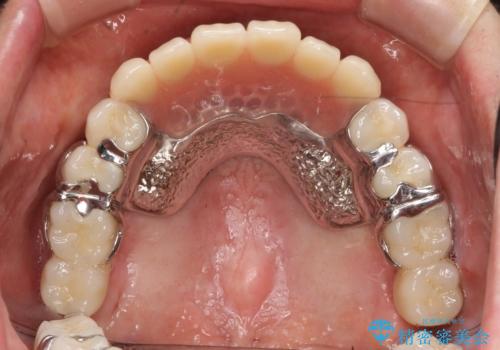

歯周病 インプラントによる咬合機能回復

- 歯が全体的にグラグラし、しっかりと物が噛めなくなり歯周病治療を希望され来院されました。

残すことのできる歯、残すことのできない歯を初期治療を進めながら見極め、最終的に臼歯部はインプラント、上顎前歯は入れ歯による補綴計画となりました。